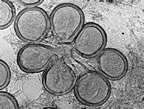

| 1-Klinik ve veteriner mikrobiyoloji alanlarında flamentli mikrofungusları tanımlamak için kullanılan deyim. 2-Genel kullanım şekli ile şapkalı mantar. 3-Mikroskopik yada makroskopik olan parazit, saprofit yada simbiyoz olarak yaşayan, klorofilsiz, zehirli yada zehirsiz olan canlı yapı. |